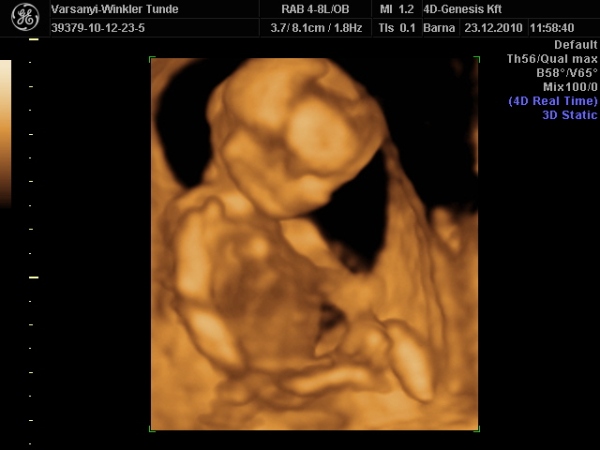

)2010.12.23 11:37